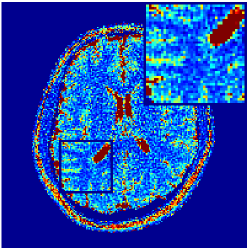

Two sets of experiments were conducted here: first, we used the 2D and 3D acquisition sequences for scanning a healthy volunteer’s brain (real-world acquisitions). Figures 6 and 7 display the parametric maps reconstructed from 2D spiral and radial readouts. We computed the T1, T2 and proton density (PD) maps using baseline reconstruction algorithms ZF, VS, LR, FLOR, AIR-MRF and our proposed LRTV. While baselines use DM either for quantitative inference or also during reconstruction (i.e. AIR-MRF), we further compare the DM-free LRTV’s performance when cascaded to DM, KM and MRFResnet for quantitative inference. For the 3D spiral acquisitions we compared LRTV and its closest competitor VS in Figure 8. Outcomes from other tested algorithm are displayed in the supplementary materials (Figure S5). Since FLOR does not use dimensionality-reduction, our system ran out of memory during 3D reconstruction; hence results are not reported in this case.

VI-E1 Discussion

The LRTV-DM and LRTV-MRFResnet perform on par, and both outperform all tested baselines for reconstructing T1, T2 and PD maps in all acquisition schemes. This can be observed both visually in Figures 6, 7, 8, S2 and S3, and quantitatively in Table IV across all tested metrics. Other baselines were unable to successfully remove the under-sampling artefacts in TSMIs, and these errors propagated to the parameter inference phase and resulted in inaccurate maps. Temporal-only priors incorporated within LR are shown insufficient to regularise the inverse problem and LR sometimes (e.g. 2D spiral acquisitions) can admit solutions with even stronger artefacts than the model-free ZF baseline. This issue was previously studied for other non-Cartesian MRF readouts that similar to our spiral/radial trajectories, miss to sample the corners of the k-space in all timeframes (see section 2.2.2 and figure 2 in [19]). In the absence of reference for the k-space corners information, the LR iterations despite minimising the objective can converge to solutions with high-frequency artefacts, as visible in the computed maps. This highlights the need for adding an appropriate spatial-domain regularisation. FLOR reduces the LR’s artefacts but this improvement is limited because the suggested nuclear norm penalty does not incorporate an explicit spatial regularisation. Further for reducing artefacts, FLOR can introduce an undesirable bias in the computed T1/T2 maps e.g. see error maps in Figures S2 and S3. The non model-based VS baseline incorporates spatial regularisation and results in spatially smoother maps than ZF and LR, but it is unable to output artefact-free images. Further and consistent with our in-vitro experiment, we observe that VS overestimates the T2 values (e.g. in White and Grey matter regions) in tested 2D acquisitions i.e. the spatial regularisation trades off agains the quantification accuracy. The model-based AIR-MRF adds spatial regularisation through 2D/3D low-pass Gaussian filters however this trades off the sharpness of the computed maps and can increase the errors at the tissue boundaries (we searched Gaussian spreads that keep the blurs and high-frequency artefacts minimal). For our acquisition readouts, Gaussian filters performed better than disk filters of [19] for avoiding strong Gibbs artefacts. On the other hand, the spatiotemporally regularised LRTV greatly improves the TSMI reconstructions i.e. 4 dB enhancement compared to the closest competitor baseline (Table IV). This enables computing accurate and aliased-free multi-parametric inference using DM or the DM-free learning-based alternative MRFResnet as visible in Figures 6, 7, 8, S2 and S3. MRResnet and DM score competitive quantitative inference results i.e. T1 and T2 MAPE less than 5% and 9%, respectively (Table IV). KM also outputs comparably accurate T1 maps, however this shallow learning model despite having a model size larger than MRFResnet, is unable to learn accurate T2/PD quantification and it results in poor estimated maps, consistent with our observations in section VI-C.